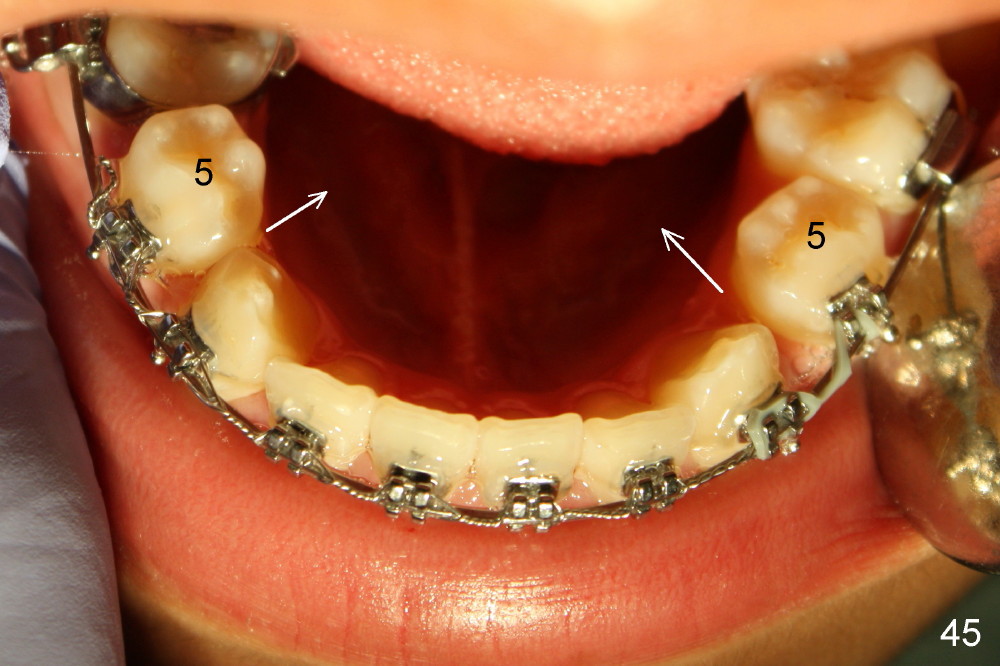

The kid returns 1 month 10 days after last visit. Wires change to 16x22 ss with figure-8 wires placed between UR3 and UL4 and between LL3 and LR 4 (Fig.41-45). A separator is placed between LL6 and 7.